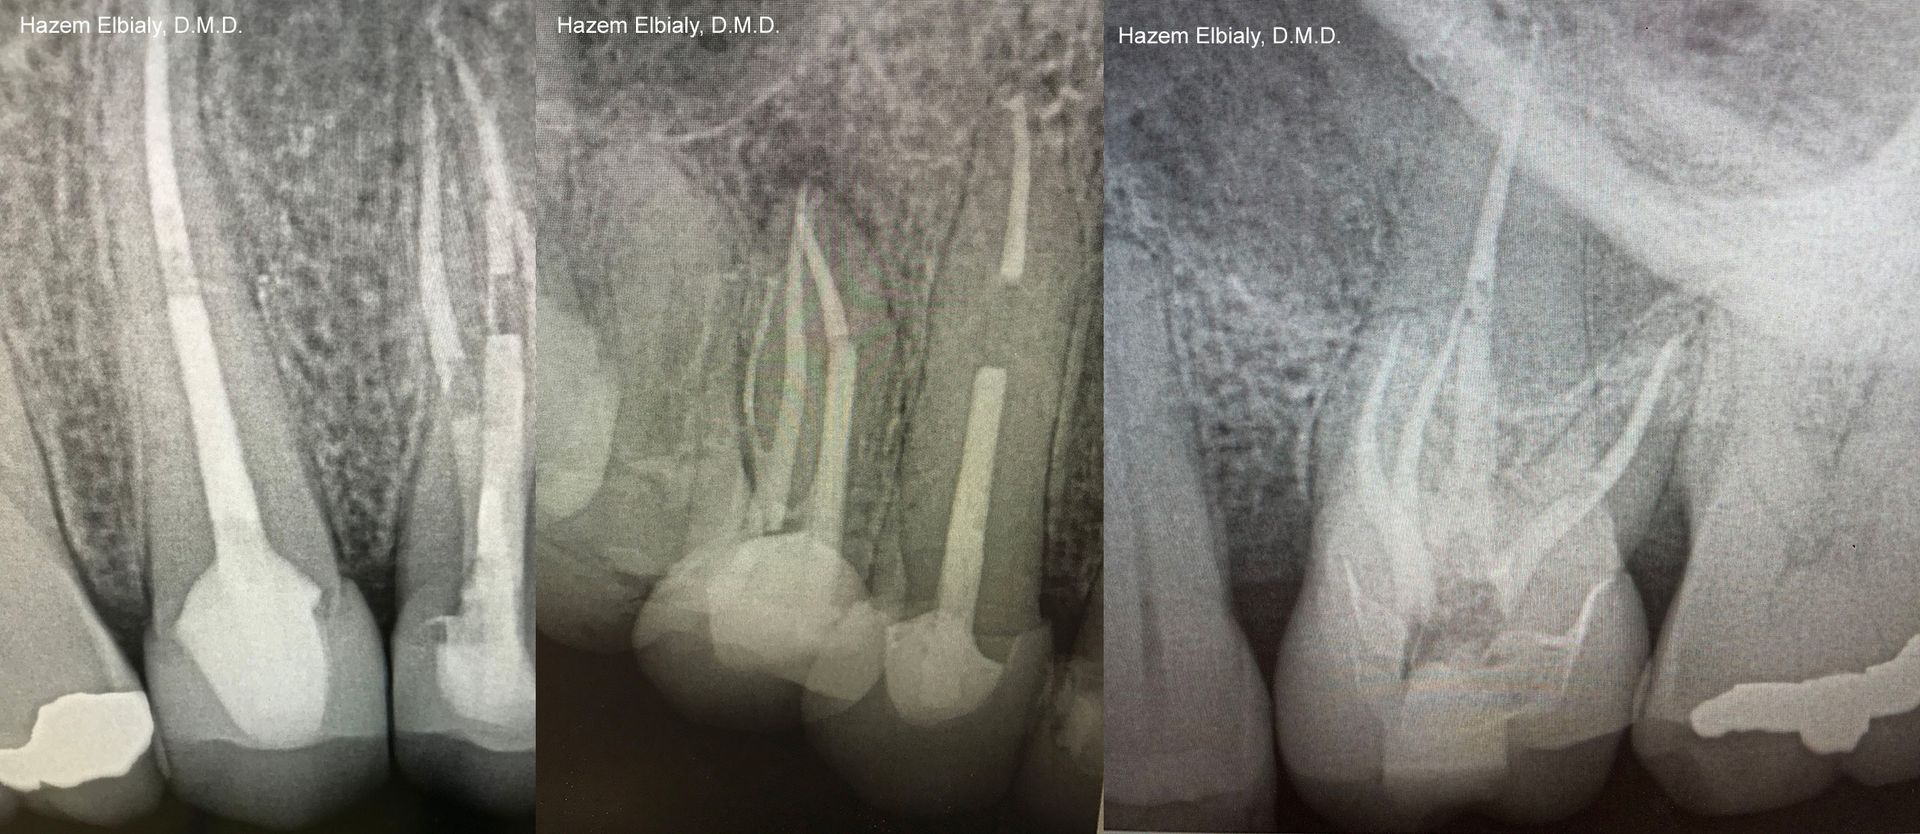

Our root canals are quick and painless. Dr. Elbialy ensures you are adequately anesthetized and comfortable before beginning the procedure. He uses an electronic apex locator and NiTi instruments for speed, pinpoint precision, and accuracy.